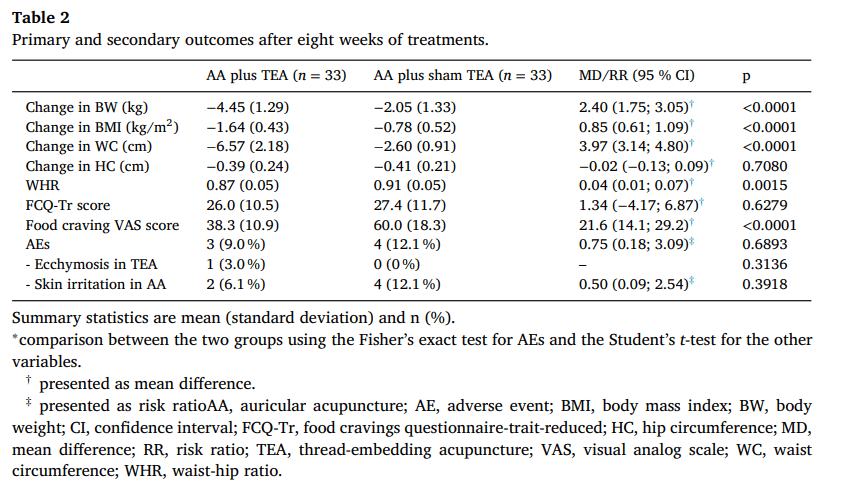

- تفاوت میانگین (MD) بین دو گروه برابر ۲.۴۰ [۱.۷۵؛ ۳.۰۵] بود (جدول ۲).

آمار خلاصه بهصورت میانگین (انحراف معیار) و تعداد (%) ارائه شده است.

- مقایسه بین دو گروه با استفاده از آزمون دقیق فیشر برای عوارض جانبی (AEs) و آزمون تی دانشجویی برای سایر متغیرها.

- † بهصورت تفاوت میانگین ارائه شده است.

- ‡ بهصورت نسبت خطر ارائه شده است.

- AA: طب سوزنی گوش | AE: عوارض جانبی | BMI: شاخص توده بدنی | BW: وزن بدن | CI: فاصله اطمینان | FCQ-Tr: پرسشنامه ولع غذایی | HC: دور باسن | MD: تفاوت میانگین | RR: نسبت خطر | TEA: طب سوزنی کاشت نخ | VAS: مقیاس بصری ولع غذایی | WC: دور کمر | WHR: نسبت دور کمر به دور باسن

نتایج ثانویه

شاخص توده بدنی (BMI) و دور کمر (WC) نیز کاهش مداوم را نشان دادند. اگرچه کاهش دور کمر در گروه AA + TEA پس از هشت هفته تفاوت معناداری با گروه AA + TEA ساختگی نداشت (ضمیمه ۳)، اما کاهش معنادار بیشتری در هر دو شاخص در گروه AA + TEA مشاهده شد (شکل ۲-A, B). پس از هشت هفته، تفاوت میانگین (MD) و فاصله اطمینان ۹۵٪ (CI) بین گروه AA + TEA و AA + TEA ساختگی برای BMI و WC به ترتیب ۰.۸۵ (۰.۶۱؛ ۱.۰۹) و ۳.۹۷ (۳.۱۴؛ ۴.۸۰) بود (جدول ۲).

کاهش دور باسن (HC) در گروه AA + TEA پس از یک هفته از شروع مداخله کمی بهتر بود اما در مجموع، تغییرات قابلتوجهی در هر دو گروه مشاهده نشد (شکل ۲-C, جدول ۲). بنابراین، نسبت دور کمر به دور باسن (WHR) از هفته پنجم درمان در گروه AA + TEA کاهش معناداری نشان داد (MD [95% CI] = 0.04 [0.02; 0.07]) (شکل ۲-D, جدول ۲).

پرسشنامه ولع غذایی (FCQ-Tr) و مقیاس بصری ولع غذایی (VAS) در طول دوره مداخله در هر دو گروه کاهش یافت. با این حال، فقط مقیاس VAS در گروه AA + TEA کاهش معناداری بیشتری نسبت به گروه AA + TEA ساختگی داشت (MD [95% CI] = 21.6 [14.1; 29.2]) (شکل ۲-E, F, جدول ۲).

در مجموع ۷ مورد عارضه جانبی (AE) ثبت شد. یک مورد کبودی در نقطه Siman پس از TEA مشاهده شد که پس از دو هفته برطرف شد. ۶ مورد دیگر شامل تحریک پوستی در نقاط AA بودند که پس از برداشتن چسب درمانی، خودبهخود برطرف شدند. تمام عوارض جانبی خفیف بودند و بدون نیاز به درمان خاصی رفع شدند (جدول ۲).